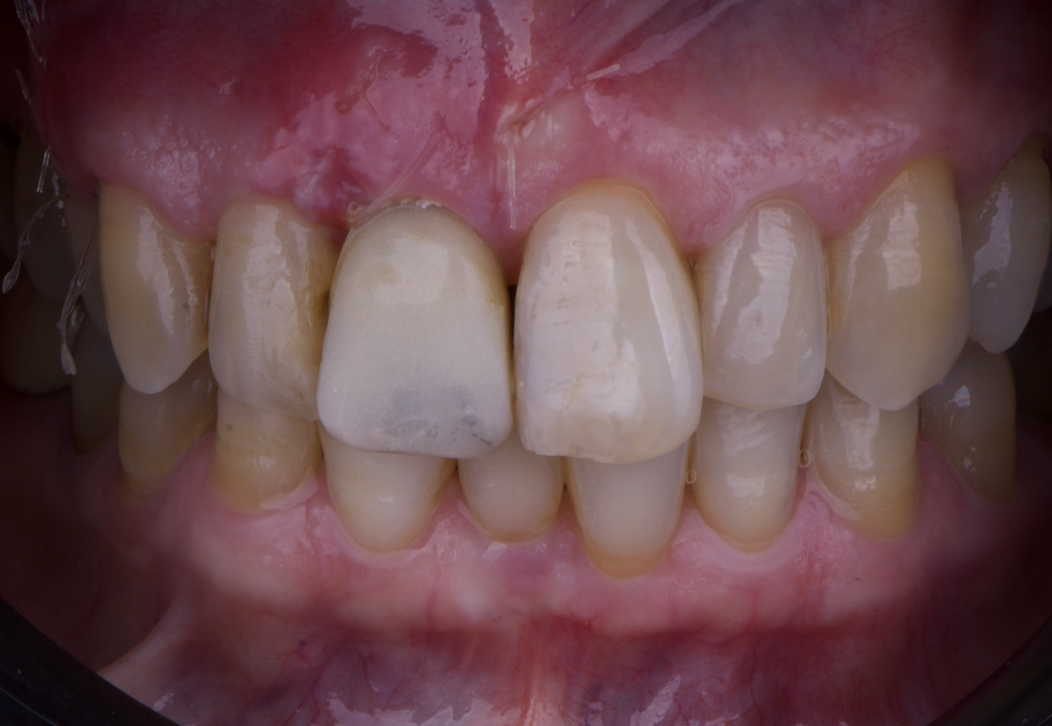

After an appropriate healing period, the definitive prosthesis was planned and delivered. A screw-retained zirconia crown was fabricated to ensure long-term durability, optimal esthetics, and retrievability. Zirconia was selected for its mechanical strength and excellent esthetic properties, blending seamlessly with the adjacent natural dentition in both form and color.

The final crown was designed to maintain the gingival architecture that had been shaped by the provisional. Special attention was paid to the emergence profile, contact points, and translucency to achieve harmony with the patient’s smile. The definitive restoration provided functional stability and esthetic integration, fulfilling the patient’s expectations for a fixed and natural solution.